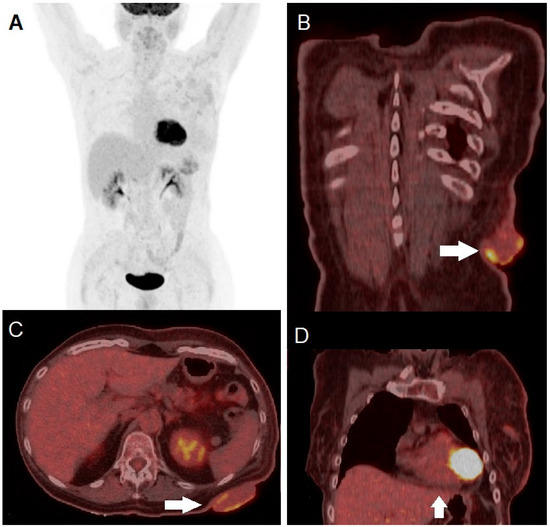

It Looks Like a Zebra but Is Not: [18F]FDG PET/CT in a Giant Cutaneous Malignant Melanoma Mimicking Squamous Cell Carcinoma

Proietti, I.; Azzella, G.; Dirzu, D.; Di Cristofano, C.; Bagni, O.; Potenza, C.; Filippi, L. It Looks Like a Zebra but Is Not: [18F]FDG PET/CT in a Giant Cutaneous Malignant Melanoma Mimicking Squamous Cell Carcinoma. Diagnostics 2024, 14, 2860. https://doi.org/10.3390/diagnostics14242860